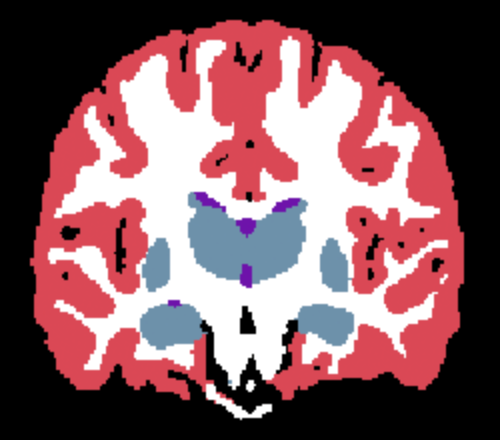

| (a) Input | (b) Ground Truth | (c) Supervised | (d) SAMSEG | (e) Naive SynthSeg | (f) Learn2Synth |

Results. Qualitative segmentation results are presented in Figure 3 and quantitative results are summarized in Table 5. Figure 3 shows that Learn2Synth produces cleaned and more accurate segmentation results compared to SAMSEG and naive SynthSeg, which is further validated by the higher Dice scores reported in Table 5. Learn2Synth also obtains higher Dice scores than the two SynthSeg variants that incorporate real data. These results highlight the effectiveness of Learn2Synth in enhancing segmentation quality for complex real-world data.